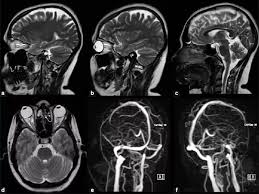

За повідомленням інтернет видання Ancient Origins, вченим вдалось провести унікальне дослідження кісної тканини внутрішнього вуха мавпи за допомоги комп"ютерної 3D томографії.

"Півкружні канали, що знаходяться у черепі між нашим мозком та вухом мають вирішальне значення для забезпечення нашого відчуття рівноваги та положення тіла під час руху. Вони забезпечують фундаментальний компонент нашого пересування, про який більшість людей, скоріш за все, не здогадується", - пояснює Інан Чжан, аспірант Інститута палеології та палеоантропології хребтових Китайської академії наук та ведучий автор статті, опублікованої в журналі "Інновація".

Вперше черепи люфенгпітеків були знайдені у Китайській провінції Юньнань на початку 1980-х років. В той час сильна деформація черепів приховали кісну область вуха, тож це стало на заваді досліджень на довгі роки.

Сучасні вчені з IVPP і Юньнаського інституту реліквій та археології (YICRA) використали новітні технології тривимірного сканування, аби створити віртуальну реконструкцію черепів. Отримані скани порівняли зі сканами, зібраними у інших тварин та доісторичних мавп та людей з Азії, Європи та Африки. Результатом аналізу стала можливість провести вже доведену паралель між особливостями устрою тіла люфенгпітеків та сучасної людини.

"Більш низькі глобальні температури сприяють пришвидшенню змін кісткового лабіринту, що свідчить про швидкий темп розвитку мавп та локомоторну еволюцію людини в цілому", пояснюють дослідники.